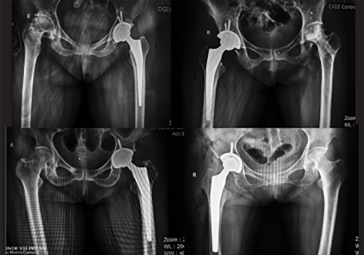

· 精準(zhǔn)執(zhí)行手術(shù)方案,消除徒手操作誤差。

· 精準(zhǔn)高效執(zhí)行手術(shù)操作,實(shí)時安裝角度顯示,誤差控制在1°以內(nèi)。